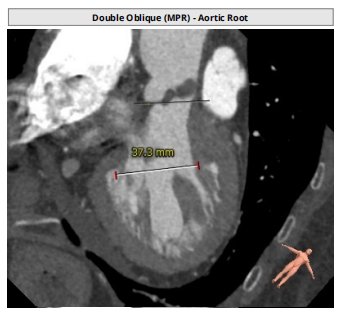

术前CT评估

整体情况

瓣环:16.9mm,左室流出道:16.7mm

STJ:23.9mm,升主动脉:31.4mm

瓣叶增厚 右冠高度:10.9mm,左冠高度:9.5mm